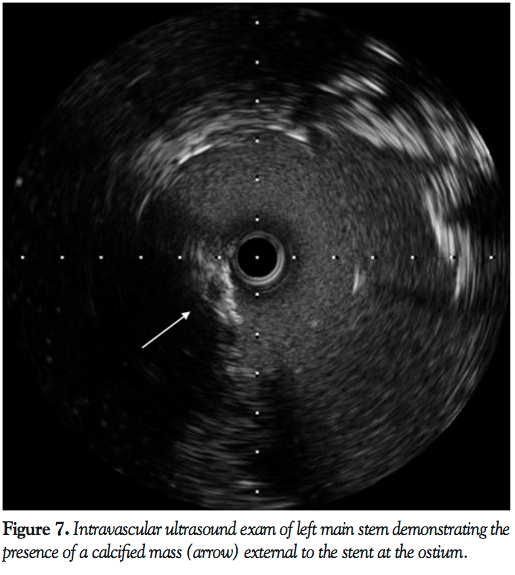

PCI was planned. To facilitate transfer and angiography, CPR using an automated load distributing chest compression device (Autopulse, Zoll Circulation) was commenced. The patient was emergently intubated and transported to the catheter laboratory. The AutoPulse gave excellent hemodynamic support (Figure 4) as compared with no support, assessed by invasive arterial pressure monitoring, and allowed uninterrupted CPR during transfer to the catheter laboratory table. Coronary angiography revealed subtotal occlusion of the LMS by a calcified mass with TIMI 2 flow (Figure 5). During automated chest compressions with AutoPulse, angioplasty guidewires were positioned in the left anterior descending and circumflex arteries and after predilatation with a 2.5 mm x 15 mm compliant balloon the LMS was stented with a 4 mm x 12 mm Integrity Resolute device (Medtronic) (Figure 6). This immediately restored TIMI 3 flow in the left coronary artery and was followed by return of spontaneous circulation, allowing removal of the AutoPulse. The total period of cardiac support with AutoPulse was 38 minutes. Intravascular ultrasound (Boston Scientific) revealed a calcified mass indenting the stent lumen at the mid and proximal section. Postdilatation with a 5 mm non-compliant balloon led to improvement in the angiographic appearance of the stent. Repeat intravascular ultrasound examination demonstrated improvement in minimum lumen area and diameter, but mild residual indentation at the site of the

calcified mass (Figure 7). Peak total creatinine kinase was 789 IU/L (ref, <170 IU/L) indicating relatively modest cardiac injury. Echocardiogram showed good left ventricular function, no impairment of prosthesis function or deformation, and importantly no increase in the minor degree of paravalvular regurgitation seen on TEE immediately post deployment. She recovered well from the procedure, with no focal neurology and intact higher mental function and was discharged to home on day 11 post THV feeling symptomatically improved.